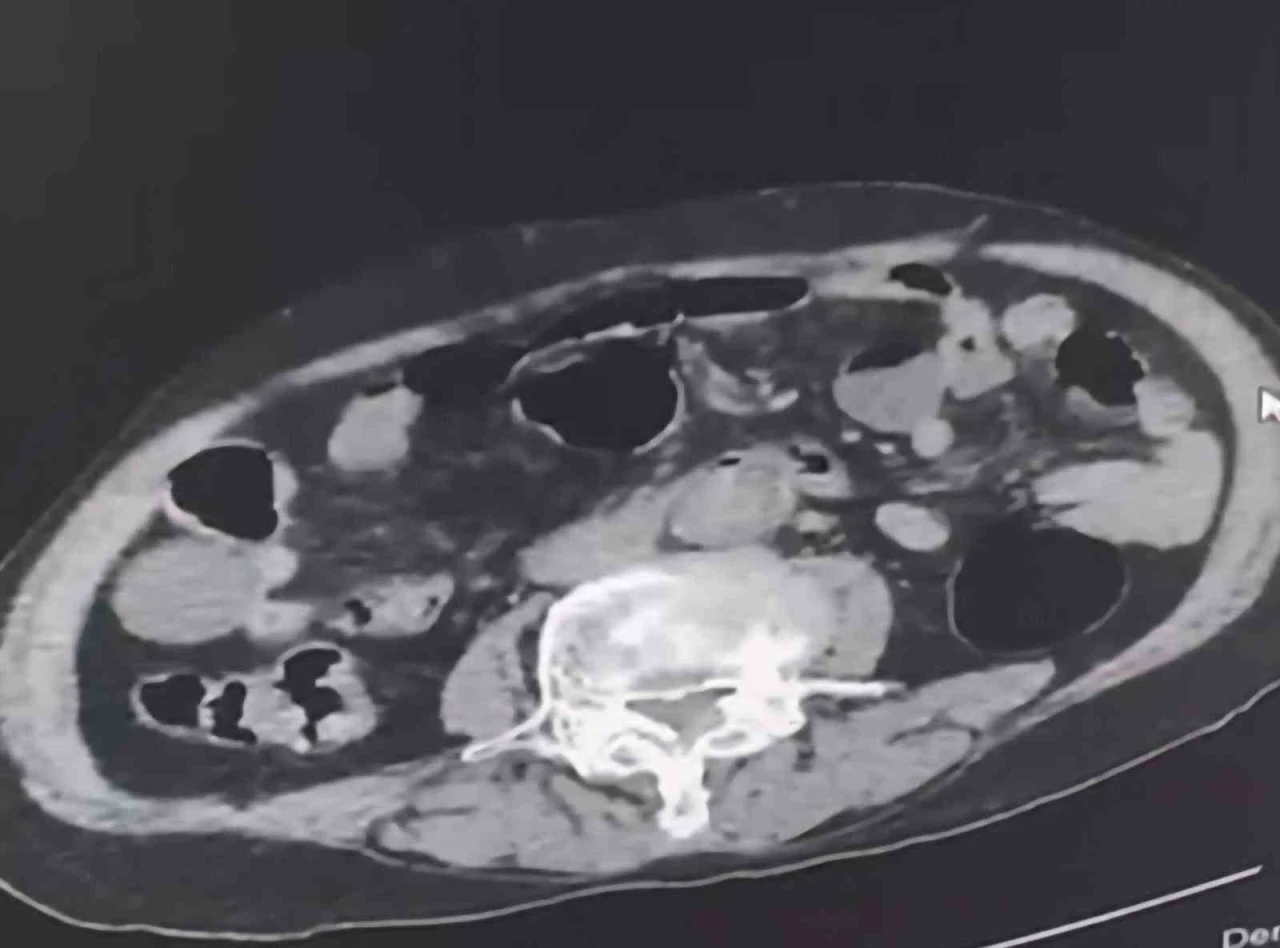

Denizli İl Emniyet Müdürlüğü Narkotik Suçlarla Mücadele Şube Müdürlüğü tarafından uyuşturucu madde ticaretinin önlenmesine yönelik yapılan çalışmalar kapsamında şehir dışından Denizli’ye uyuşturucu sokmak isteyen 2 yabancı uyruklu şahıs takibe takıldı. Takip sonrasında Denizli’de malları teslim edeceği kişi ile buluştukları esnada düzenlene operasyonla 3 şahıs gözaltına alındı. Gözaltına alınan şüpheliler üzerinde yapılan incelemelerde yabancı uyruklu bir şüphelinin uyuşturucu maddeyi cinsel organında taşıdığı belirlendi. Şüphelilerin üzerlerinde ve adreslerinden yapılan aramalarda 6 parça halinde 145 gram metamfetamin maddesi, 260 gram sıvı halde sentetik ecza maddesi ele geçirildi.